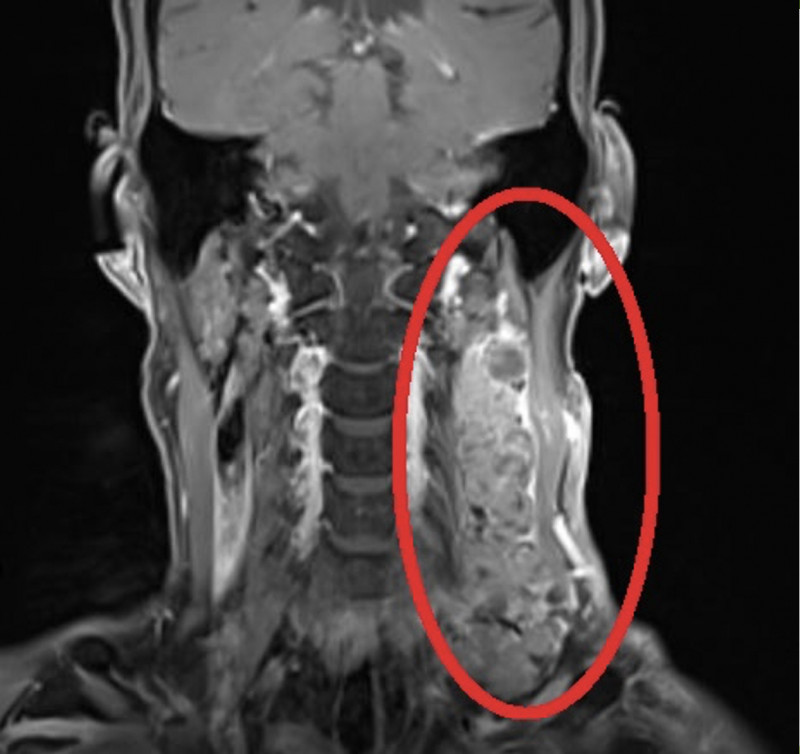

患者罹患第2期「轉移性鱗狀細胞癌」,頸部左側有12X5公分的長巨型腫瘤。(記者蔡淑媛翻攝)

〔記者蔡淑媛/台中報導〕台中一名60歲馬拉松好手,今(2026)年刮鬍子時發現頸部左側微腫,就醫檢查赫然發現是12X5公分的巨型頸部腫瘤,確診罹患第2期「轉移性鱗狀細胞癌」,成長快速,腫瘤靠近鎖骨上頸動脈,不易發現又危險,醫師提醒,發現頸部不明原因無痛卻持續變大腫塊,應立即就醫,及早發現治療。

鄧政宗醫師指患者罹患「轉移性鱗狀細胞癌」,頸部左側有12X5公分的長巨型腫瘤,且緊臨頸動脈。(記者蔡淑媛攝)

鄧政宗醫師患者罹患「轉移性鱗狀細胞癌」,頸部左側有12X5公分的長巨型腫瘤。(記者蔡淑媛翻攝)